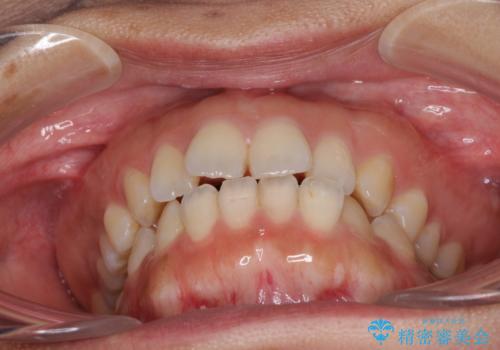

全く目立たないワイヤー矯正 上下リンガル矯正

- 上下の前歯のでこぼこを気にして来院された患者様です。

結婚式が近いこともあり、全く目立たない裏側矯正により口元を整えることとしました。

下顎が左側にずれているため、裏側矯正ということもあり咬み合わせを整えるのに時間がかかってしまいました。